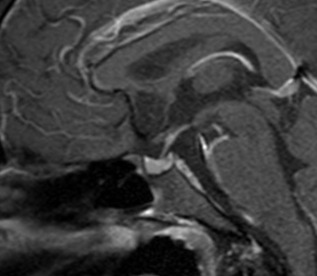

USG, TC e RN de tireoide